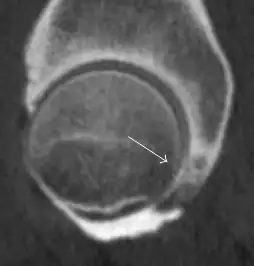

Radiological signs of transient osteoporosis of the hip include localized osteoporosis of the femoral head and neck (Figure 8). Nevertheless, final diagnosis has to be made with MRI to differentiate it from avascular necrosis and from insufficiency or stress fractures of the femoral head or neck. In case of AVN, radiographs can only demonstrate delayed or advanced signs. Staging according to Ficat classification ranges between normal appearance (stage I), slight increased density in the femoral head (stage II), subchondral collapse of the femoral head with or without “crescent” sign (stage III), and advanced collapse with secondary osteoarthritis (stage IV). In the case of stress or insufficiency fractures X-ray sensitivity has been proven to be much lower than MRI, which is currently the gold standard.[1]

Figure 8:

-

X-ray of a patient with transient osteoporosis of the left hip showing osteoporosis.[1] -

Coronal stir imaging in transient osteoporosis, showing diffuse edema.[1] -

Scintigraphy (A), sagittal T1 (B), and coronal PD fat sat of a patient with a subchondral fracture of the femoral head with convex shape to the articular surface.[1] -

Coronal T1 of a patient with avascular necrosis of the femoral head.[1]

Intra-articular osseous causes of pain include several conditions: avascular necrosis (AVN), transient osteoporosis of the hip (TOH), tumors, and stress or insufficiency fractures. All these entities may present with a pattern of bone marrow edema characterized by decreased signal intensity on T1 weighted images and increased signal intensity on fluid sensitive sequences, such as fat saturated T2-weighted or STIR images. When there is no evidence of a focal lesion associated with the edema pattern, TOH is suspected. When a band of low intensity is seen inside the edematous area, the shape and length of this band become important. It is generally convex to the articular surface in the case of subchondral stress or insufficiency fractures, whereas it is concave, circumscribing all of the necrotic segment, in cases of AVN. When doubts do persist, gadolinium-enhanced MRI tends to show that the proximal portion beyond the band is enhanced in fractures but is not in AVN.[1]